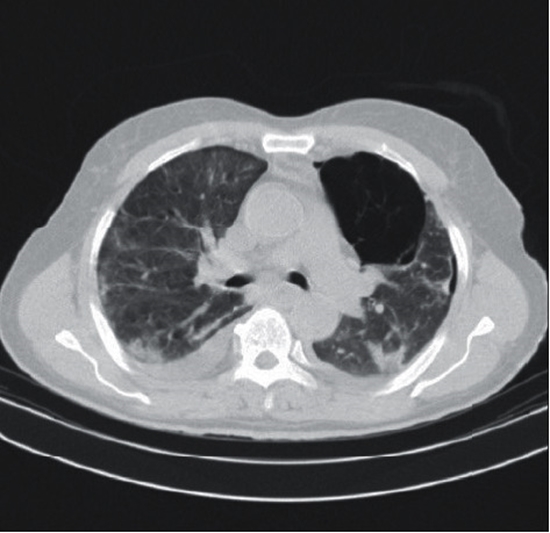

Case presentation: A 79-year-old male with acute abdominal pain, nausea, and vomiting presented to the emergency department of our hospital. He was diagnosed with myelodysplastic syndrome 7 years ago, for which he took thalidomide and erythropoietin as the main medications. The prominent findings of the physical examination were hypotension, tachycardia, fever, mild hypoxemia, and epigastric and right upper quadrant tenderness of the abdomen. Except for mildly increased creatinine and lipase, other laboratory findings were in concordance with myelodysplastic syndrome. Due to the patient's oliguria, the computed tomography (CT) scan was performed without contrast, which, together with the ultrasonography, raised the clinical impression of acute pancreatitis. The patient's hypotension was refractive to supportive treatment, resulting in progressive deterioration of the clinical condition. A later contrast-enhanced CT scan suggested microvascular ischemia of the duodenum. An emergent Whipple's procedure was planned initially, which was later switched to a damage control surgery due to the patient's cardiac arrest during the surgery. Despite all the supportive therapy provided at the intensive care unit, the patient expired of a cardiac arrest which occurred two hours after the termination of the surgery.